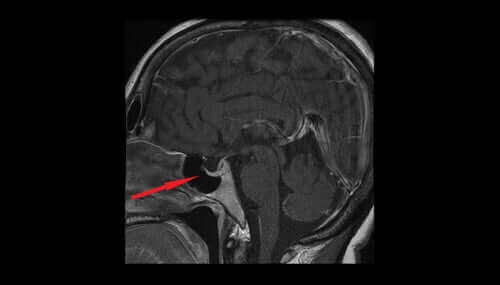

In dit artikel zullen we kijken naar de verschillende kenmerken en effecten van vasopressine. Vasopressine, ook bekend als antidiuretisch hormoon of ADH, komt uit de magnocellulaire kernen van de hypothalamus.

Het antidiuretisch hormoon dat vrijkomt uit hypothalamische neuronen heeft met de regulering van bloeddruk en temperatuur te maken. Er zijn aanwijzingen dat dit hormoon pijnstillende effecten kan hebben, die van seks en stress afhankelijk zijn.

Overmatige niveaus van dit antidiuretische hormoon kunnen optreden als gevolg van de bijwerkingen van medicijnen en long-, borstwand-, hypothalamus- en hypofyse-aandoeningen.

Lage niveaus van het antidiuretisch hormoon zorgen ervoor dat de nieren overtollig water uitscheiden. Het urinevolume zal toenemen en zal tot uitdroging en een verlaging van de bloeddruk leiden. Lage niveaus van het antidiuretische hormoon kunnen dus op schade aan de hypothalamus of hypofyse of primaire polydipsie duiden.

In dit artikel zullen we kijken naar de verschillende kenmerken en effecten van vasopressine. Vasopressine, ook bekend als antidiuretisch hormoon of ADH, komt uit de magnocellulaire kernen van de hypothalamus.